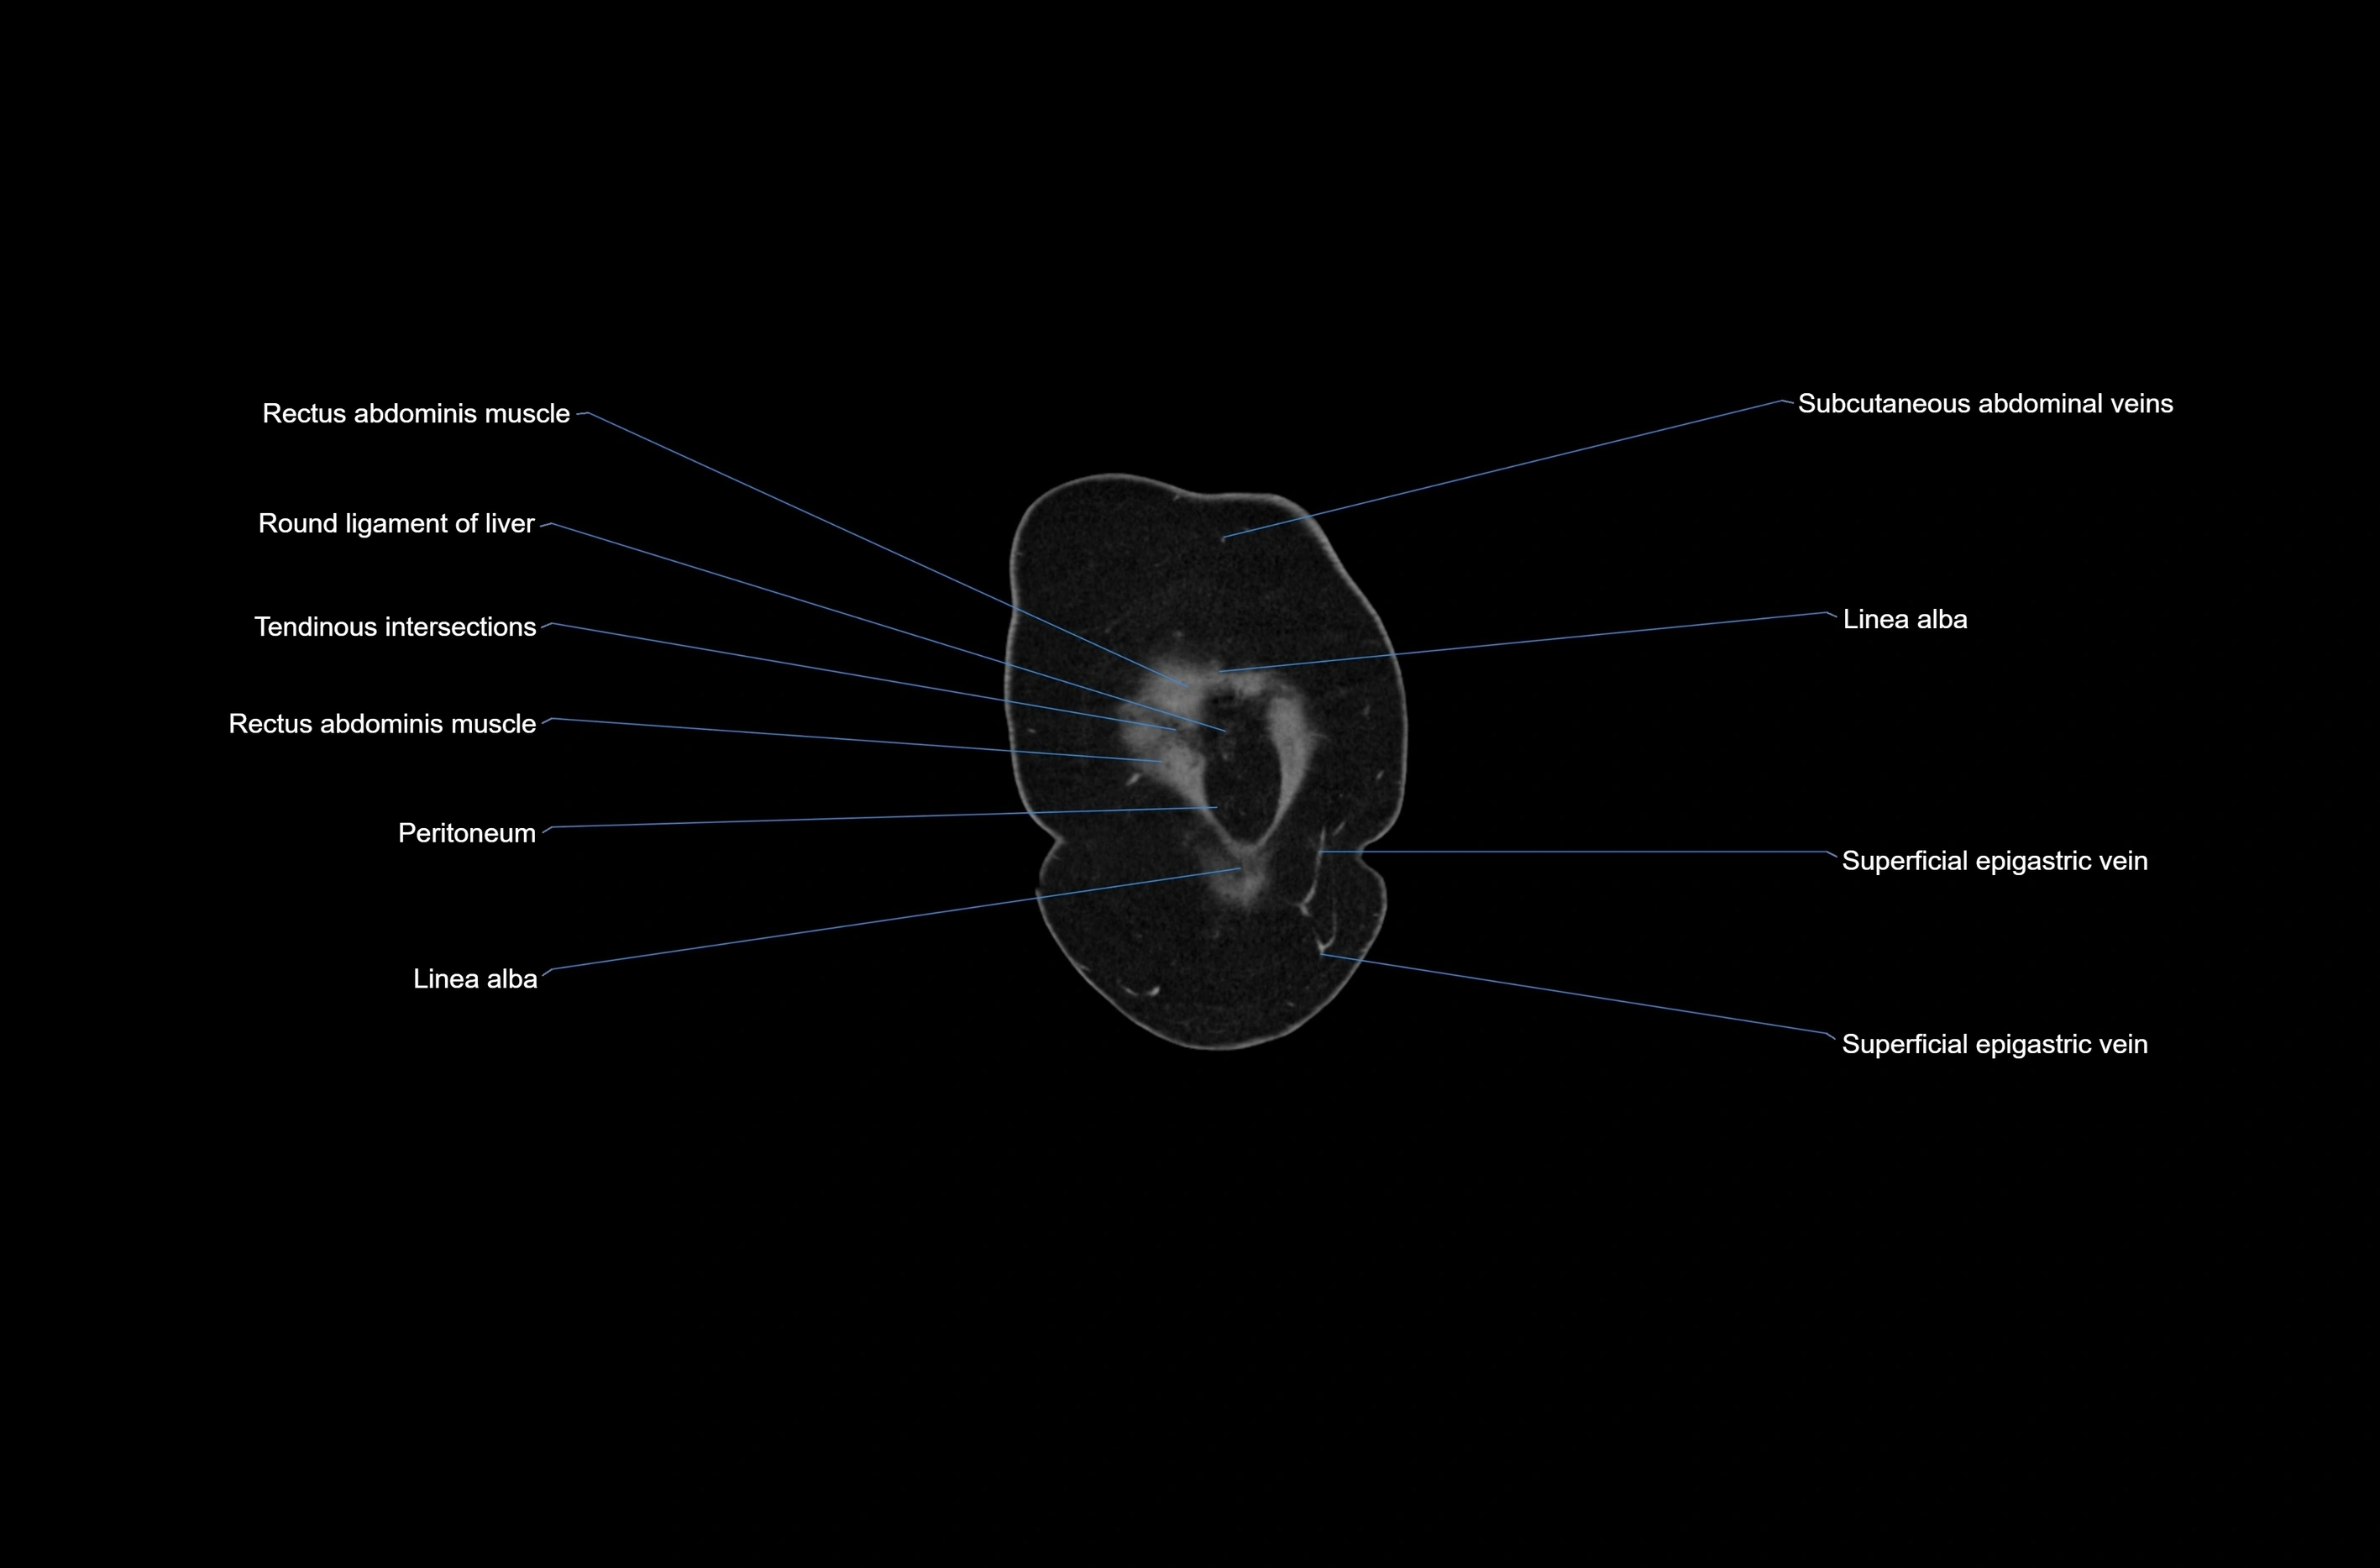

- Linea alba

- Rectus abdominis muscle

- Umbilical vein